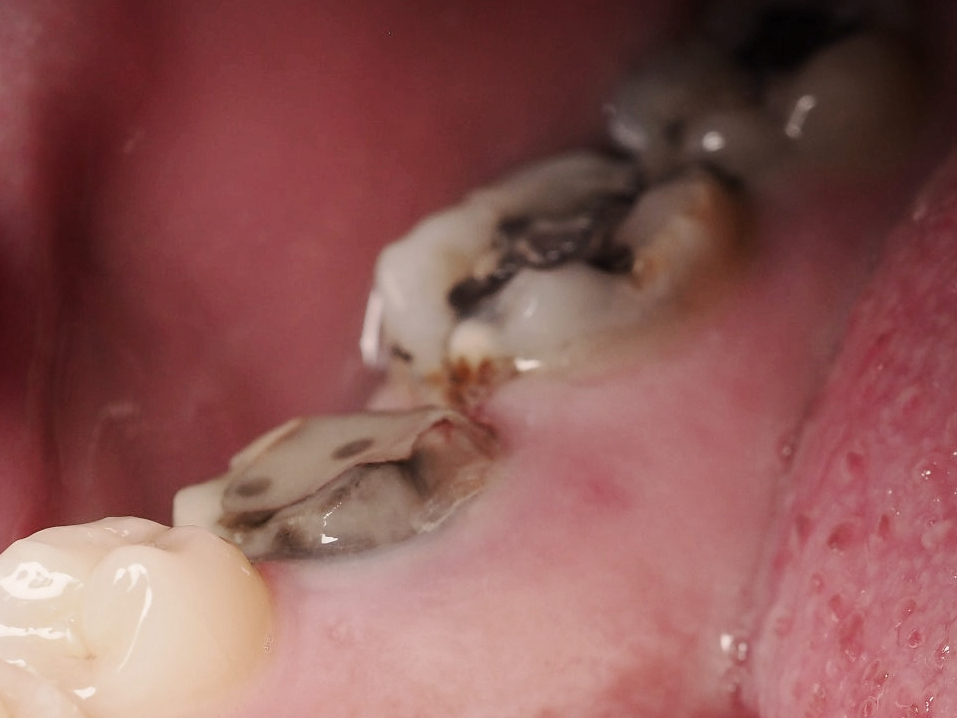

- 충전물과 치아 사이 틈이 생긴 경우

마곡치과_치아와 충전물 경계 틈

이건 눈에 잘 안 보입니다.

그래서 더 중요합니다.

시간이 지나면

아말감과 치아 사이에

아주 미세한 틈이 생길 수 있습니다.

그 틈 사이로 세균이 들어가면?

겉은 멀쩡.

속은 충치 진행 중.

벽지는 멀쩡한데

속에 곰팡이 생기는 느낌.

입안에도…

조용한 사건 사고가 있습니다.